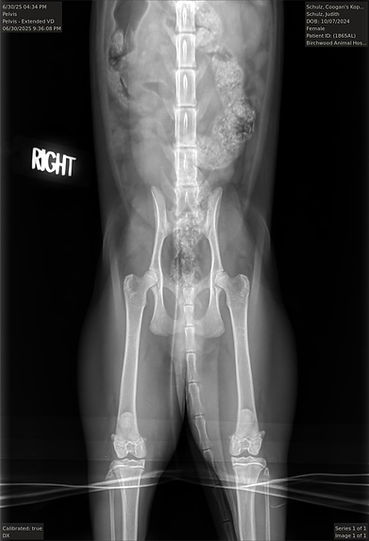

HD: Pass with both hips "Excellent" and "Good"!

Hips: X-ray below:

Hips: Pawpeds Right 1, Left 1